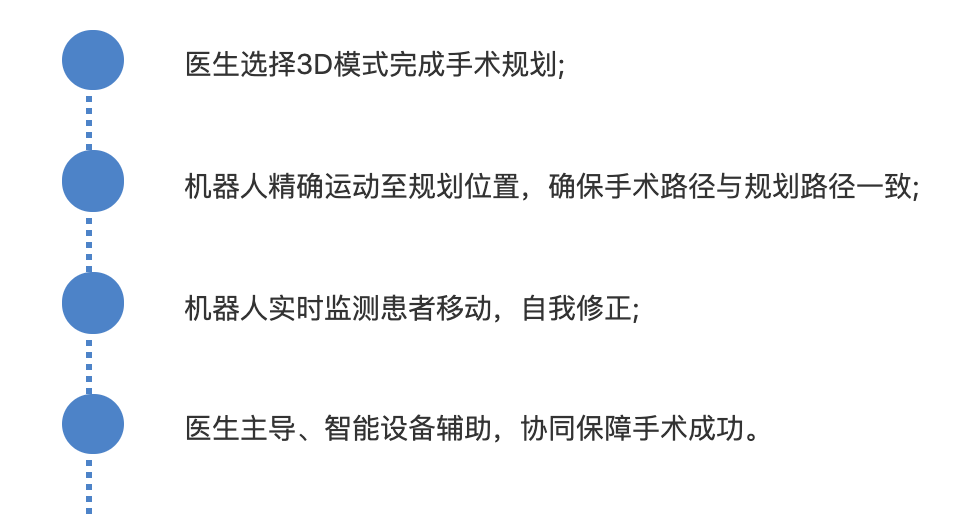

Š▒čŔőĆšČČń║îňĆ░ÔÇťňĄęšÄĹÔǣڬʚžĹŠť║Šó░ń║║ňĚ▓ŔÉŻŠłĚń╗üŠůłňżÉňĚ×ń╗üŠůłňî╗ÚÖó2019ň╣┤11ŠťłńŞşŠŚČň╝ĽŔ┐ŤŠ▒čŔőĆšťüšČČń║îňĆ░ňĄęšÄĹ?ڬʚžĹŠëőŠť»Šť║Šó░ń║║��´╝î5ńެŠťłŠŚÂÚŚ┤ڬʚžĹ9ńެšŚůňî║ňů▒ň«îŠłÉŠť║Šó░ń║║Šîçň»╝ńŞőŠëőŠť»131ńżő��´╝îňîůŠőČŔâŞŔů░ŠĄÄڬʊ՜ŠĄÄńŻôŠłÉňŻóŠť»��´╝îš╗ƚܫÚĺëŠúĺňćůšëóڣኝ»��´╝îŔéíÚ¬ĘÚółÚ¬ĘŠŐśňŐáňÄőŔ×║ÚĺëšëóÚŁá��´╝îń╗ąňĆŐŔłčÚ¬Ęڬʊ՜Ŕ×║ÚĺëšëóÚŁáŃÇüŔéíÚ¬ĘňĄ┤ňŁĆŠş╗ňçĆňÄőŠĄŹÚ¬ĘŃÇüŔâźÚ¬Ęň╣│ňĆ░ڬʊ՜ňŐáňÄőŔ×║ÚĺëšëóÚŁáŃÇüŔĚčÚ¬ĘŔĚŁÚ¬Ęڬʊ՜Ŕ×║ÚĺëšëóÚŁáŃÇüÚ¬ĘŔé┐šśĄŠ┤╗ŠúÇšşëŠëőŠť»����ŃÇéňĄęšÄĹ?ڬʚžĹŠëőŠť»Šť║Šó░ń║║ń╗ąň«âň╝║šŤŤšÜäňůëňşŽŔ┐ŻŔެš│╗š╗čňĺîŠôŹńŻťšĘ│ňŤ║šÜ䊝║Šó░Ŕçé��´╝îŔÁäňŐęڬʚžĹňî╗šöčš▓żňçćň«îŠłÉŠëőŠť»��´╝îňĄžňĄžŠĆÉÚźśń║ćŠëőŠť»ňçćší«ň║Ž��´╝îÚÖŹńŻÄń║ćŠëőŠť»ňŹ▒ň«│����ŃÇéňĄęšÄĹڬʚžĹŠëőŠť»Šť║Šó░ń║║šÜäň╝ĽŔ┐Ť��´╝îń╗úŔíĘŠłĹÚÖóŠÖ║ŠůžÚ¬ĘšžĹň╗║Ŕ«żňĆłŔ┐łňç║ń║ćňŁÜň«×šÜäńŞÇŠşą����ŃÇ銾皟áŠ│ëŠ║É´╝ÜňżÉňĚ×ń╗üŠůłňî╗ÚÖó